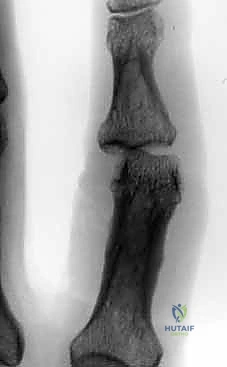

Distal K-Wire Insertion: Securing the Segment

- Identify Distal Wire Level: Under image intensifier guidance, identify an appropriate level in the distal half to two-thirds of the middle phalanx. This placement must be distal to any fracture extension in the shaft of the middle phalanx to ensure adequate purchase in healthy bone. Mark this level on the skin.

> PEARL: For pilon fractures with significant distal extension, the distal wire can be placed as far distally as the head of the middle phalanx, or even near the center of rotation of the distal interphalangeal (DIP) joint. The middle phalanx is often narrowest proximally, so a more distal placement often provides a wider bone segment for easier and more secure wire placement. I have never encountered a fracture so distal that adequate fixation could not be achieved.

Figures 1D and 1E (TECH FIG 1D,E) illustrate finding and marking the position of the distal wire. Note how this placement is more distal than average, towards the head of the middle phalanx, due to an associated DIP joint injury, providing ample bone for fixation.

-

Initial Distal Wire Insertion: Similar to the proximal wire, insert the 1.1-mm K-wire percutaneously, aiming for the center of the middle phalanx. This wire must be perpendicular to the long axis of the finger and, crucially, parallel to both the plane of rotation of the PIP joint and the previously inserted proximal wire. This parallelism is essential for creating a functional dynamic construct.

Fluoroscopic Confirmation (Partial Insertion): Insert the wire partially through the middle phalanx and check its position carefully with both PA and lateral views on the image intensifier.

*Figures 1F and 1G (TECH FIG 1F,G) confirm the insertion and position of the distal wire on the image intens